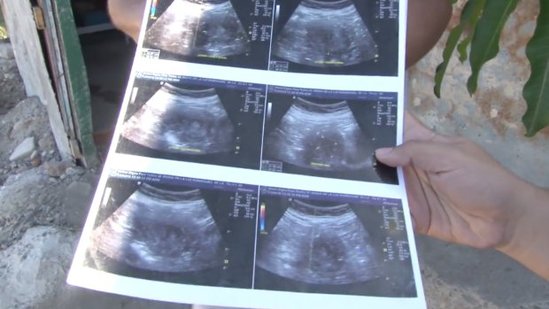

Meksikanın Sinaloa ştatının Masatlan şəhərinin sakini Mariya de la Luz 6 aylıq hamilə olduğunu bildirir.

Ariya Ultrasəs müayinəsindən keçib və qız övladı dünyaya gətirəcək.

Bundan sonra isə ultrasəs müayinədən keçib. İlk müayinədən sonra Mariya gözlərinə inanmayıb və 10 başqa klinikada da müayinədən keçib. Bütün klinikalar qadının hamilə olduğunu deyib.